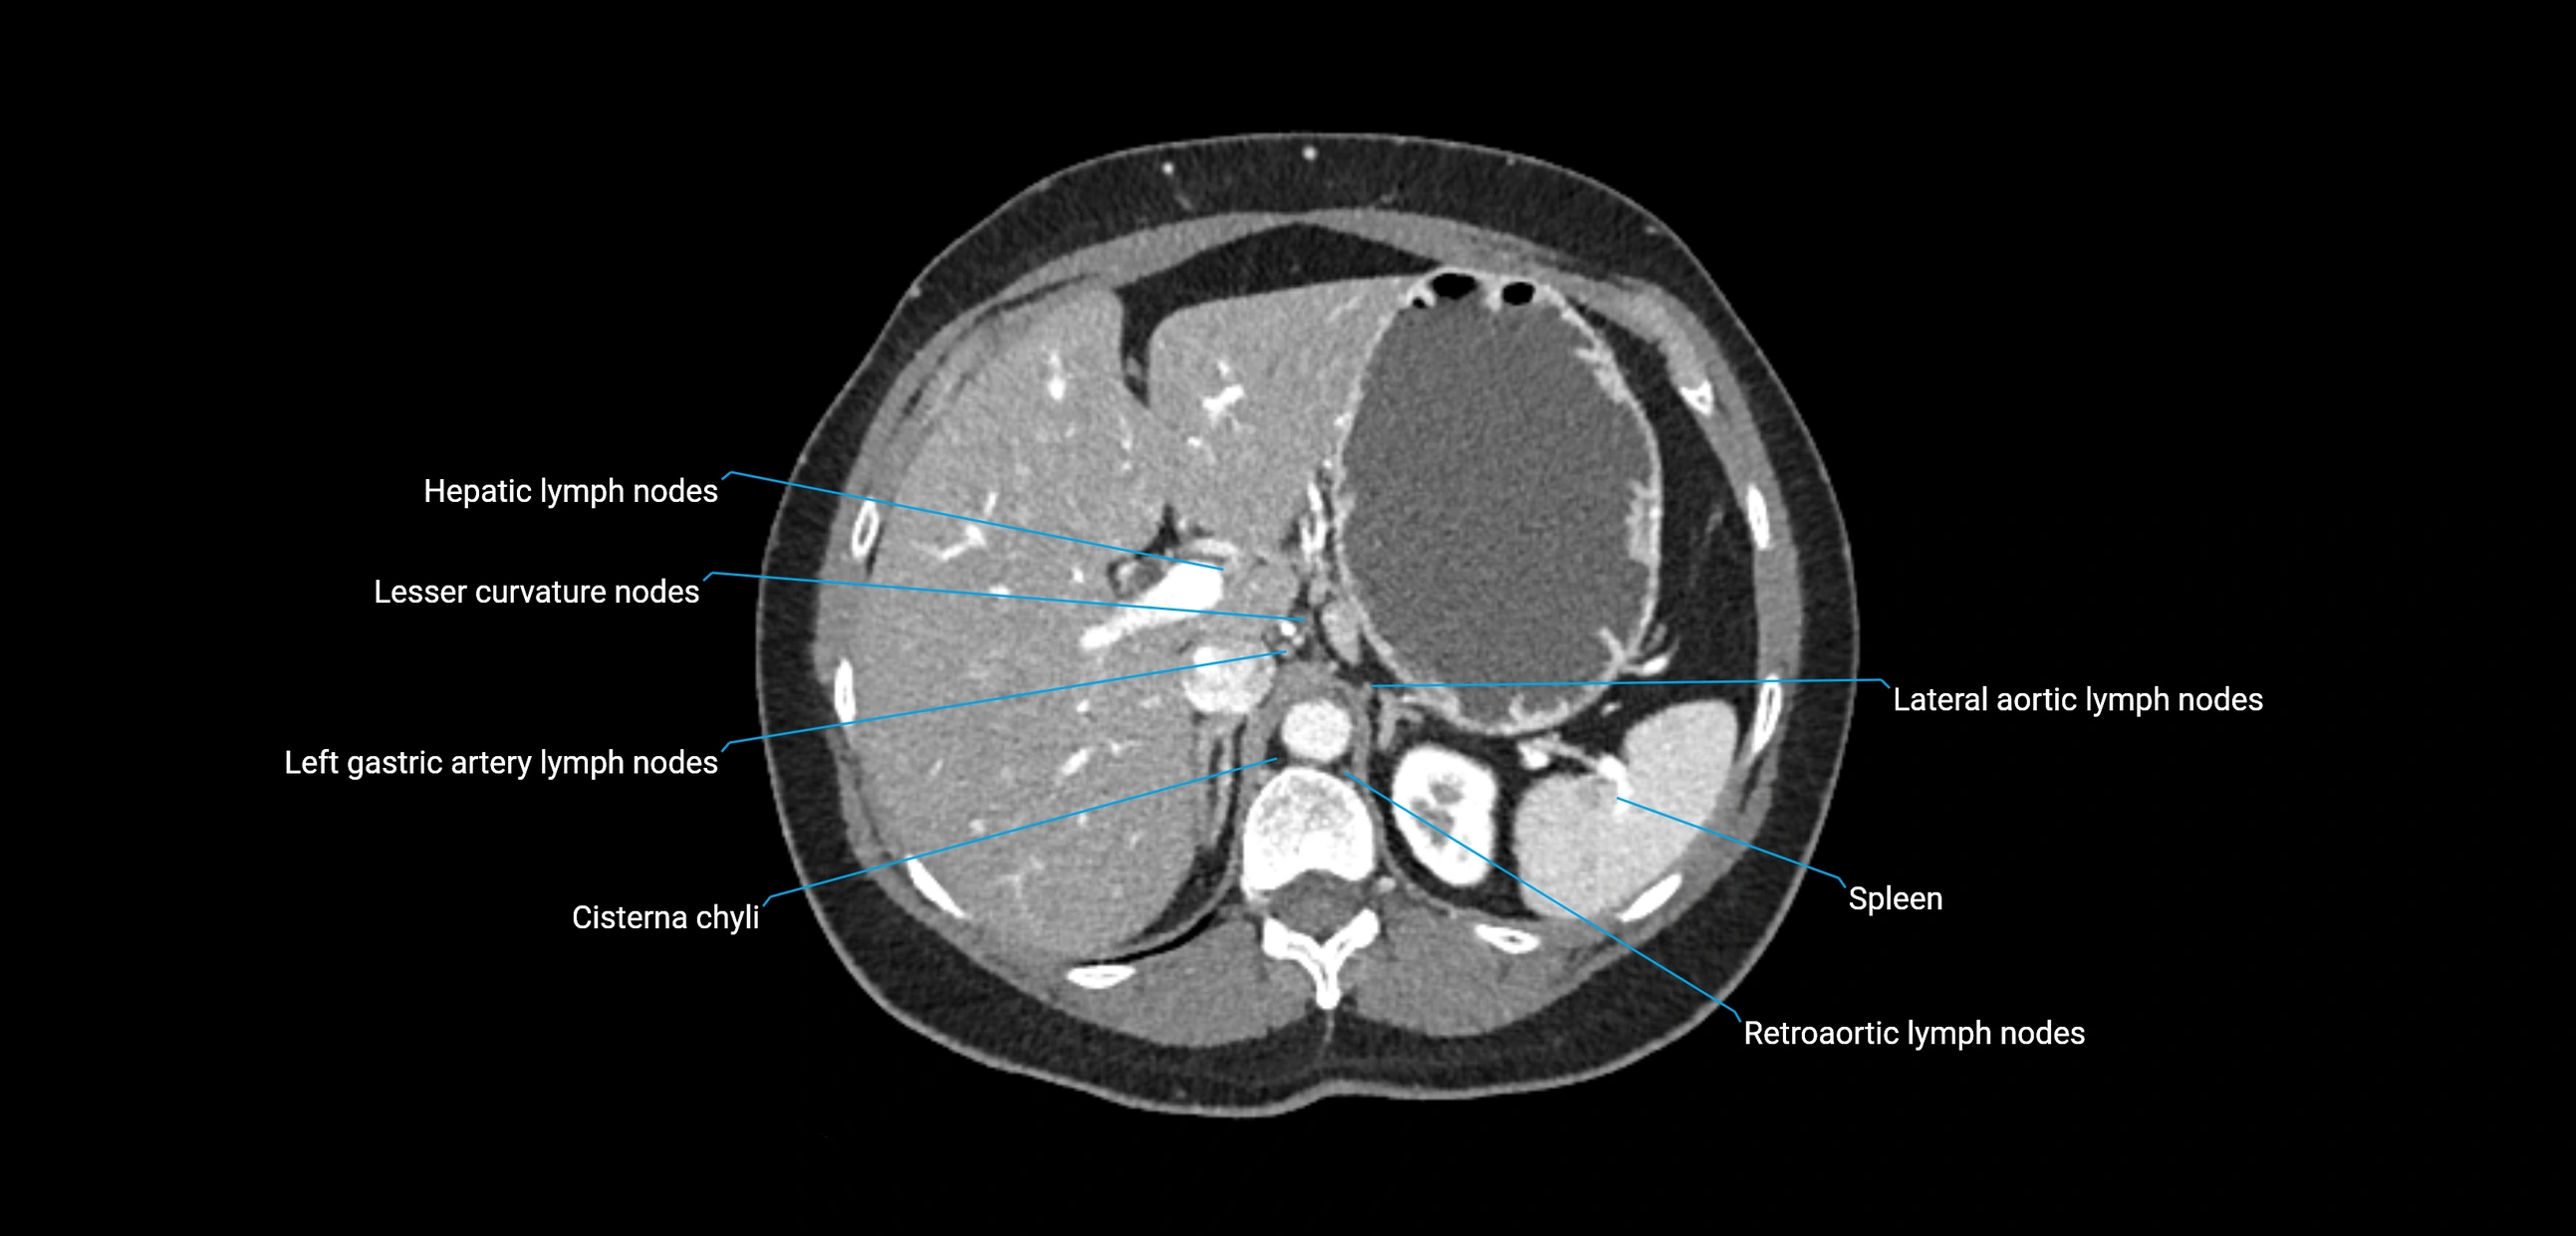

The lateral aortic lymph nodes (also called para-aortic lymph nodes) are a major group of retroperitoneal lymph nodes located along the abdominal aorta and its branches. They lie between the diaphragmatic crura superiorly and the bifurcation of the aorta at L4 inferiorly.

They are positioned on both sides of the abdominal aorta:

• Right lateral aortic nodes: adjacent to the inferior vena cava (IVC)

• Left lateral aortic nodes: lateral to the abdominal aorta

These nodes receive lymph from a wide range of abdominal and pelvic structures. Specifically, they drain lymph from the kidneys, suprarenal glands, gonads (testes/ovaries), uterus, uterine tubes, and pelvic organs, before converging into the lumbar lymphatic trunks, which terminate in the cisterna chyli → thoracic duct.

CT Appearance

CT Pre-Contrast:

• Nodes appear as soft-tissue density nodules adjacent to the aorta and IVC

CT Post-Contrast:

• Normal nodes enhance homogeneously

• Malignant nodes may show heterogeneous enhancement, central necrosis, or conglomerate formation

• Size >1 cm short axis is suspicious, though morphology and distribution are equally important

CT image

image